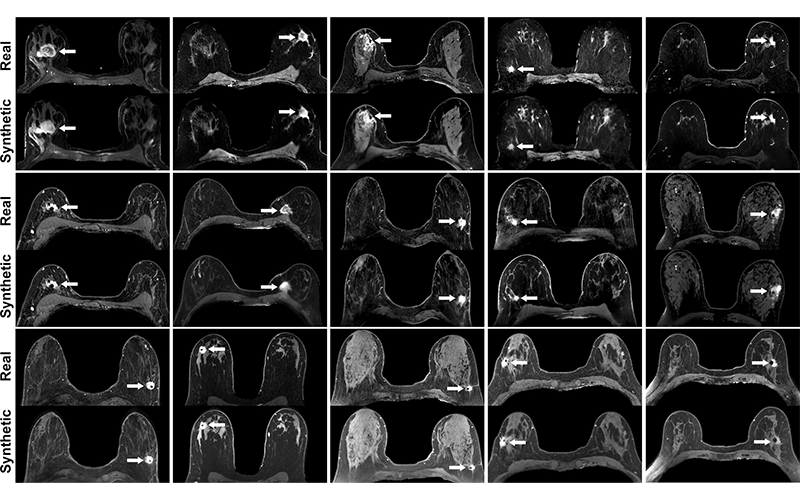

Simulated Contrast Enhanced Breast MRI RSNA Rsna Breast Imaging Screening and ai continue to be key topics in breast imaging with emphasis placed on examining overdiagnosis. Recall the characteristic us appearances of benign and malignant breast masses, including ductal carcinoma in situ. Screening, ai, ultrafast and parametric mri techniques are trending in this category. Metastatic lymph node involvement in breast cancer is a key determinant of the overall stage. Rsna Breast Imaging.